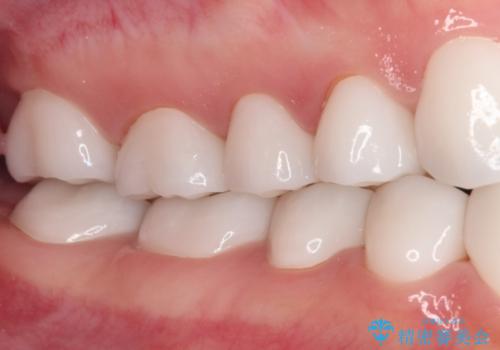

- 奥歯の銀歯をセラミックにしたいとのことで来院された患者様です。

より白さが目立つように、自然な仕上がりではなく、作り物の雰囲気があるフルジルコニアクラウンにて補綴治療を行いました。